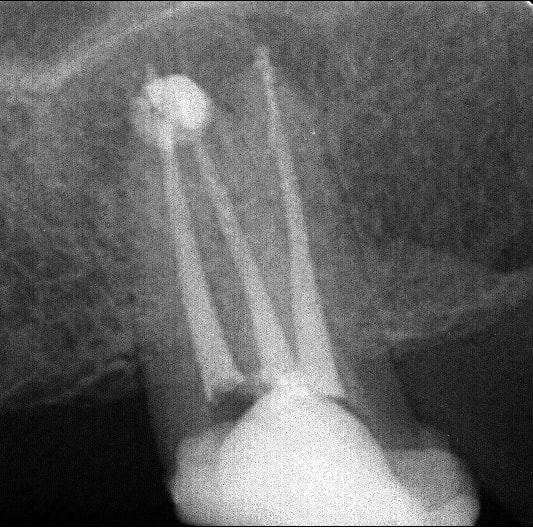

Juste pour prouver qu'on peut tout faire avec Mc Spadden, le derviche écossais:

Canal large, on est allé au F5 sans toucher les bords, cône calibré à 55 à l'apex, thermocompacteur à 3mm de la LT. Pas d'anesthésie.

Je l'utilise de mieux en mieux mais c'est vrai qu'il y a une petite douleur ressentie par les patients. Je descend super bas, mais je vérifie que j'ai un bon tug back à chaque fois (je descends à 2-4 mm de l'apex), avec un 40 ou un 30 la plupart du temps.